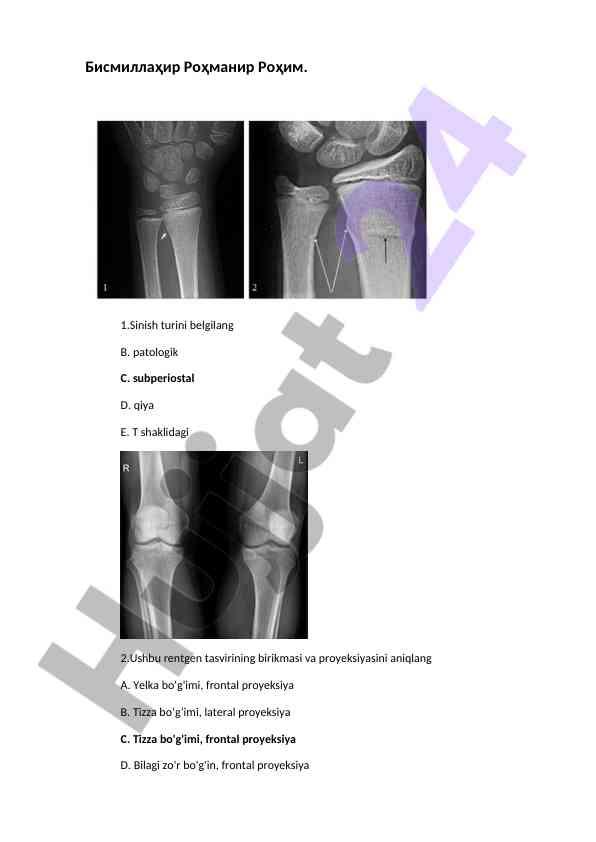

Ushbu dokumentda rentgen laboranti mutaxassisligi bo'yicha ikkinchi malaka toifasi uchun shakllantirilgan og'zaki savollar keltirilgan. Savollar rentgen nurlarining kashf etilishi tarixi, rentgen tasvirlarini olishning fizika asoslari hamda turli diagnostika usullari haqida. Bular orasida OIV infektsiyasi, radiologiya tushunchasi va ultratovush diagnostikasi kabi mavzular mavjud.